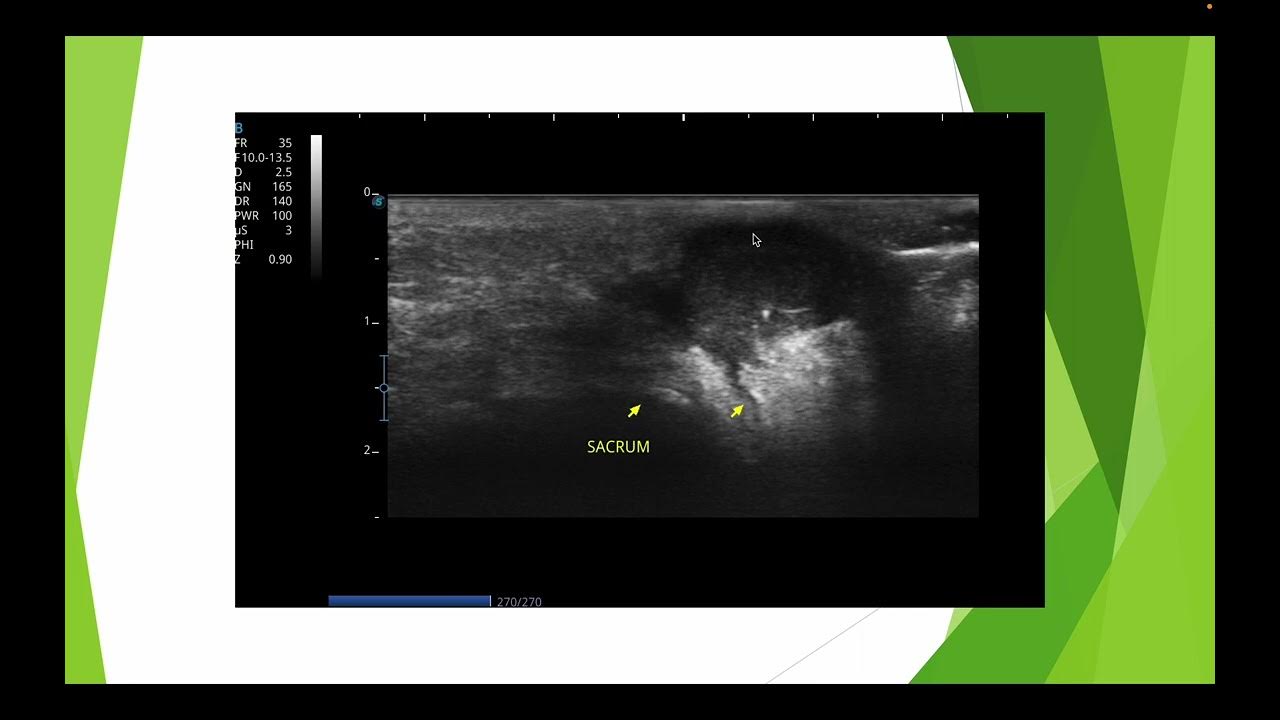

Source: ndeibsetf.pages.dev Aspect typique du kyste pilonidal en échographie YouTube , Le kyste est tellement gonflé et douloureux qu'une opération d'urgence est nécessaire Dernier message posté le : 22/09/2017 à 19h05 Profil supprimé 15/08/2017 à 17h39 Alerter Copier le lien Le lien a été copié dans votre presse-papier Bonjour! Je vous fait part de mon expérience après mon opération au laser pour mon kyste pilonidal